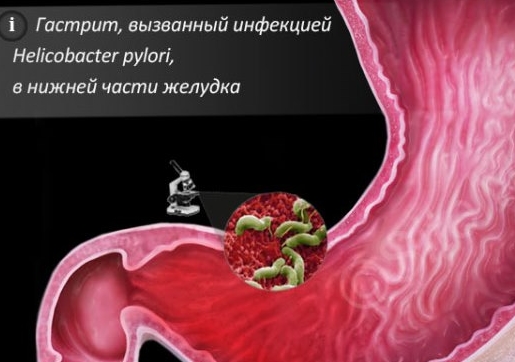

Информация и фотографии о хроническом гастрите и дуодените